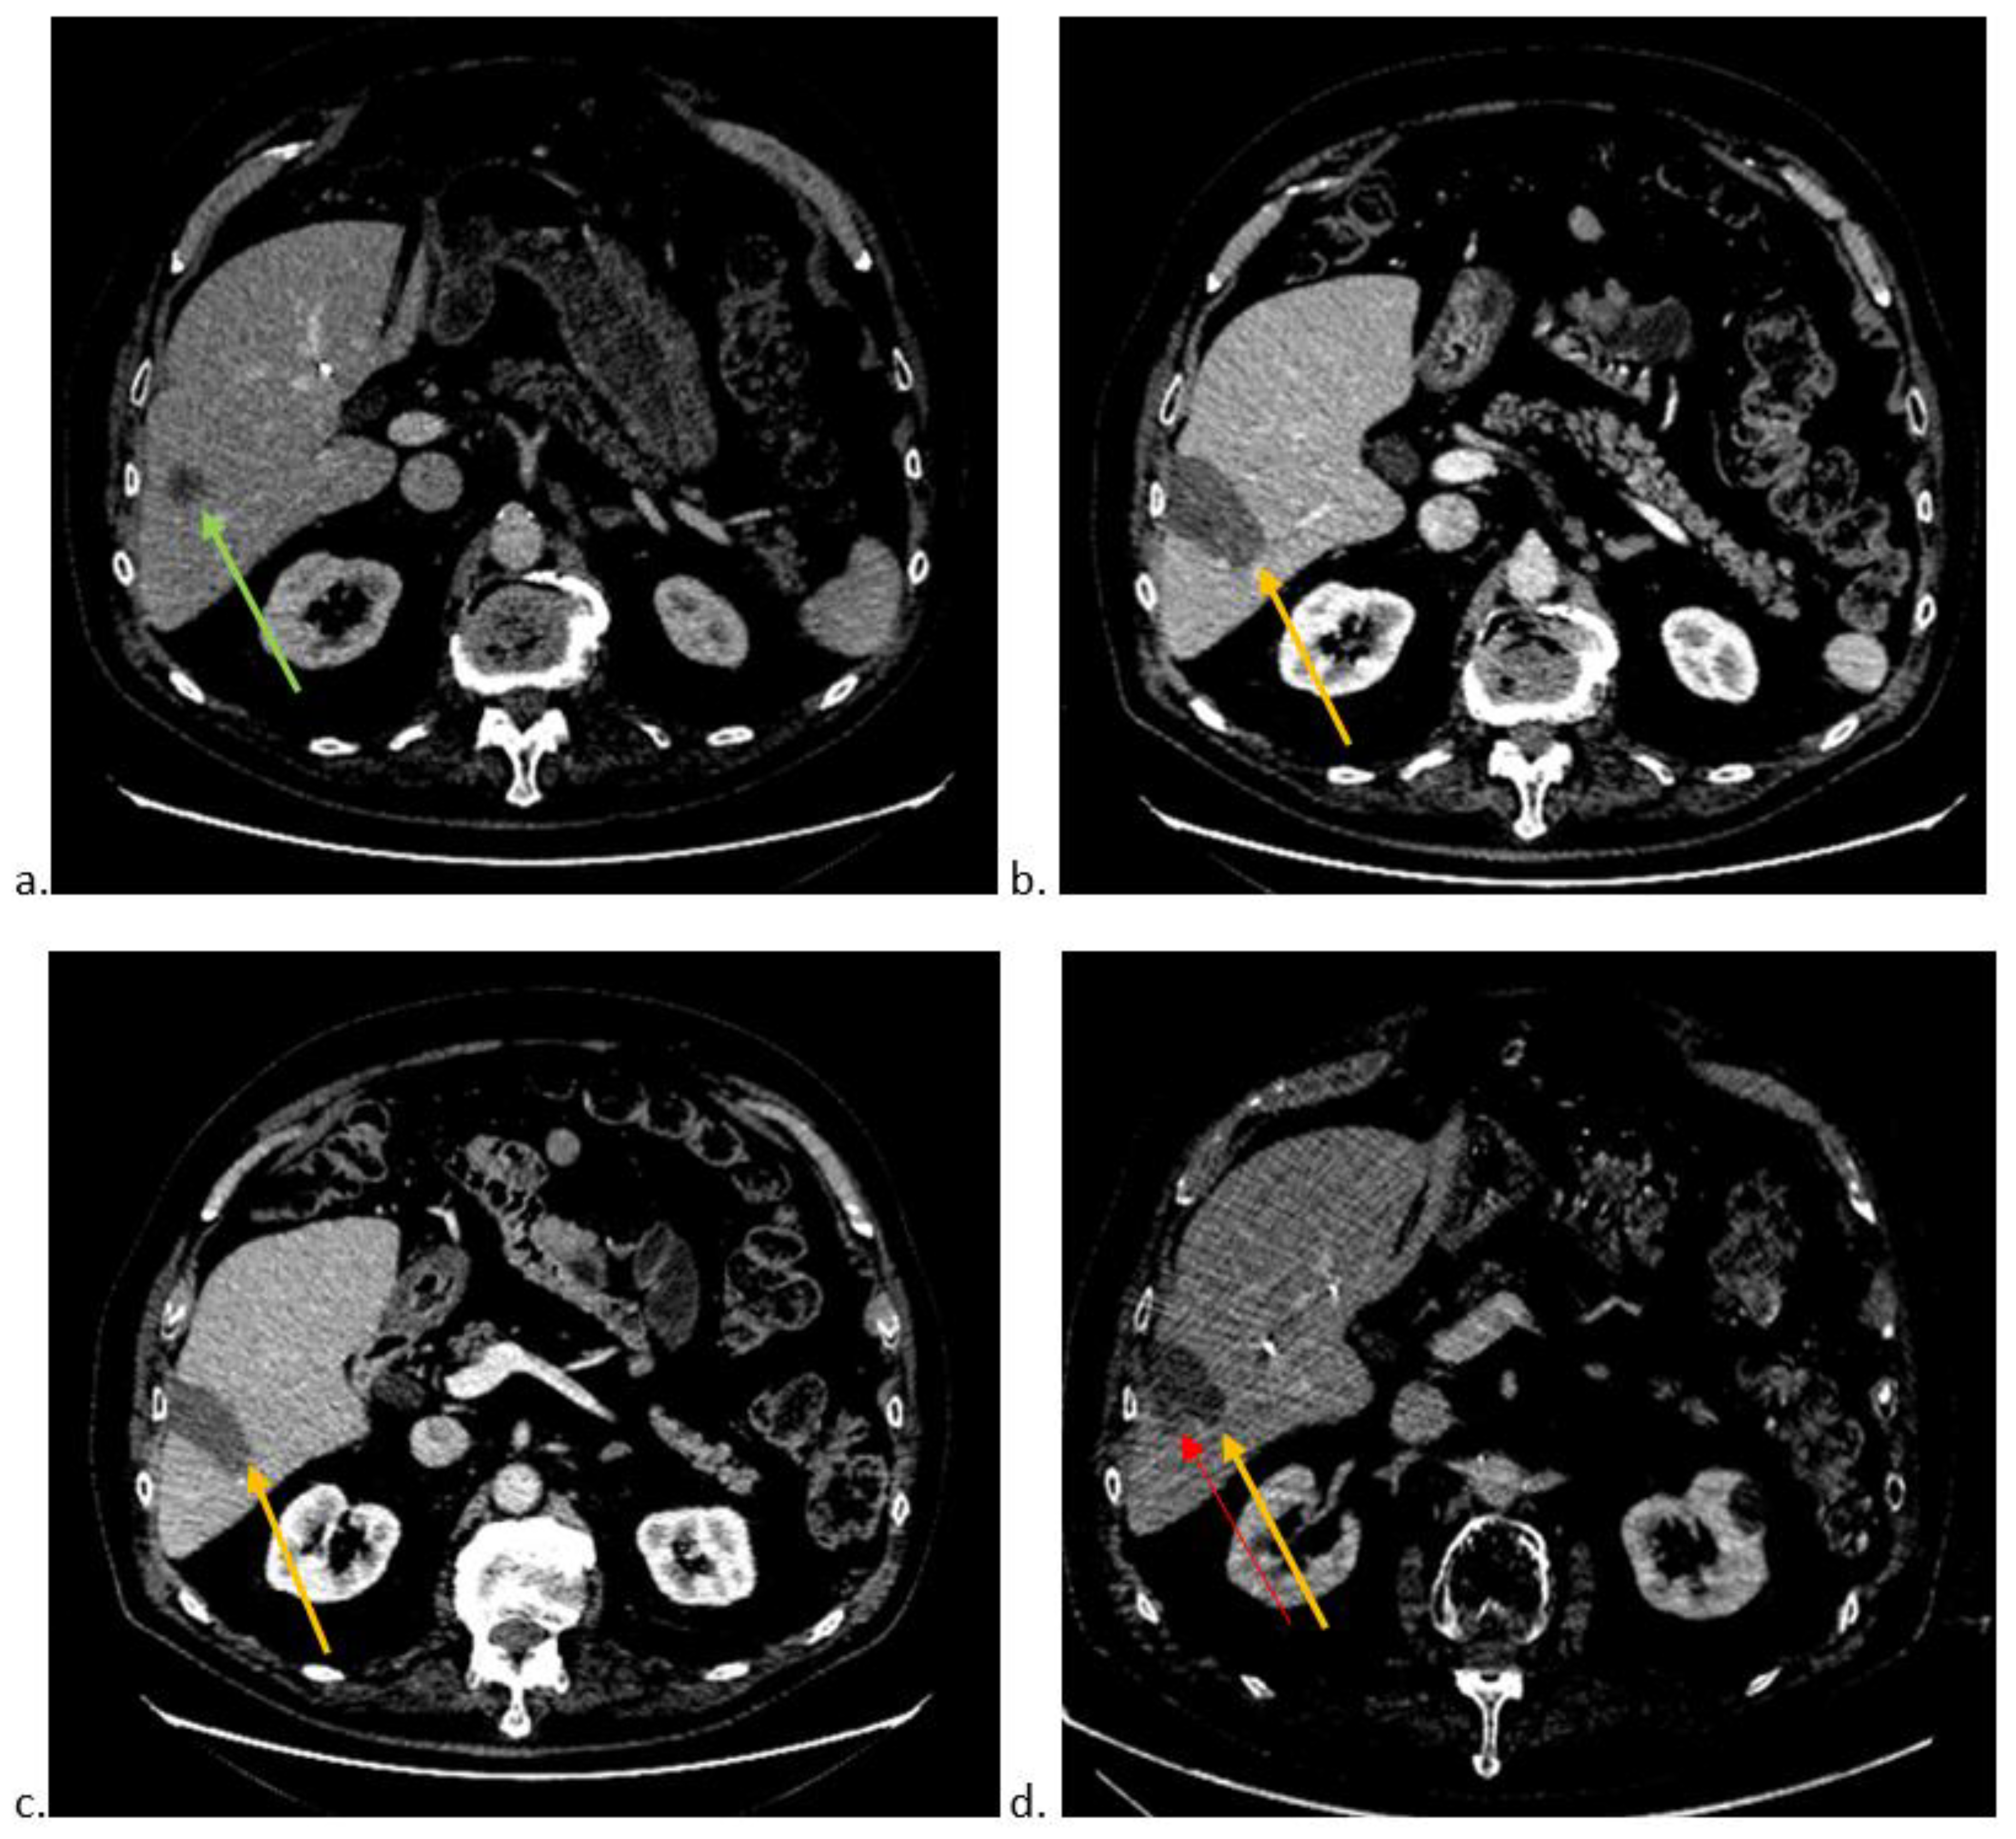

| Thermoablation site shape (non-ovoid versus ovoid) | 177 | 4.25 | [1.87–9.76] | <0.001 |